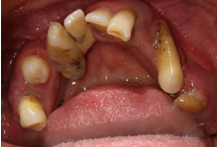

2、龋病

老年朋友根面龋比较常见。龋病在最初的时候往往没有什么症状,出现疼痛就诊时可能已经需要行去神经根管治疗了。而很多患者朋友却不在意,任龋患发展,待到就诊时牙齿很多时候都需要拔除了。治疗龋病的策略是早发现早治疗。病情进展到需要根管治疗后往往还需要修复科行冠修复,时间和经济都是种损失。而任龋病进展到需要拔牙的程度就得不偿失了。